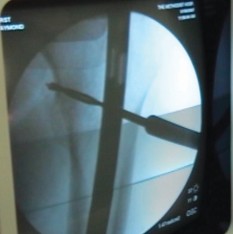

Once both canals are adequately prepared, the femur and tibia are aligned. Antegrade insertion of a modular or custom long arthrodesis nail is most common. The nail is introduced through the greater trochanter, passed down the femoral canal, across the prepared knee joint, and into the tibial canal.

Fluoroscopy is used to confirm the trajectory of the nail across the joint line to avoid posterior cortical perforation of the proximal tibia. The final nail position should be 3 to 5 inches above the tibial plafond.

Once the nail is fully seated, proximal interlocking screws are placed in the femur. Axial compression is then applied across the arthrodesis site. This can be achieved manually or via the internal compression mechanism of the nail system. After adequate compression and bony apposition are confirmed fluoroscopically, distal interlocking screws are placed in the tibia to secure the construct.